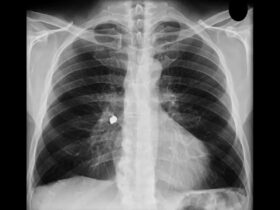

Os equipamentos permitem que os especialistas realizem procedimentos rápidos e eficazes, como a Endoscopia Digestiva Alta, que leva entre 5 a 10 minutos, e possibilita ao médico avaliar diversos sintomas, como dor abdominal, náusea, vômitos e dificuldades de engolir, sendo mais preciso que o raio-x para detectar inflamações, úlceras e tumores.

A Endoscopia digestiva alta é um exame complexo, utilizado para a detecção de diversas doenças do trato digestório. “A endoscopia digestiva alta pode indicar uma série de patologias, como esofagite, gastrite, doença do refluxo gastresofágico, câncer no esôfago, estômago ou duodeno, úlceras gástricas e úlceras duodenais. O exame também é indicado para a pesquisa do Helicobacter pylori, bactéria responsável pela maioria das úlceras e muitos casos de inflamação do estômago (gastrite crônica)”, explica o especialista.